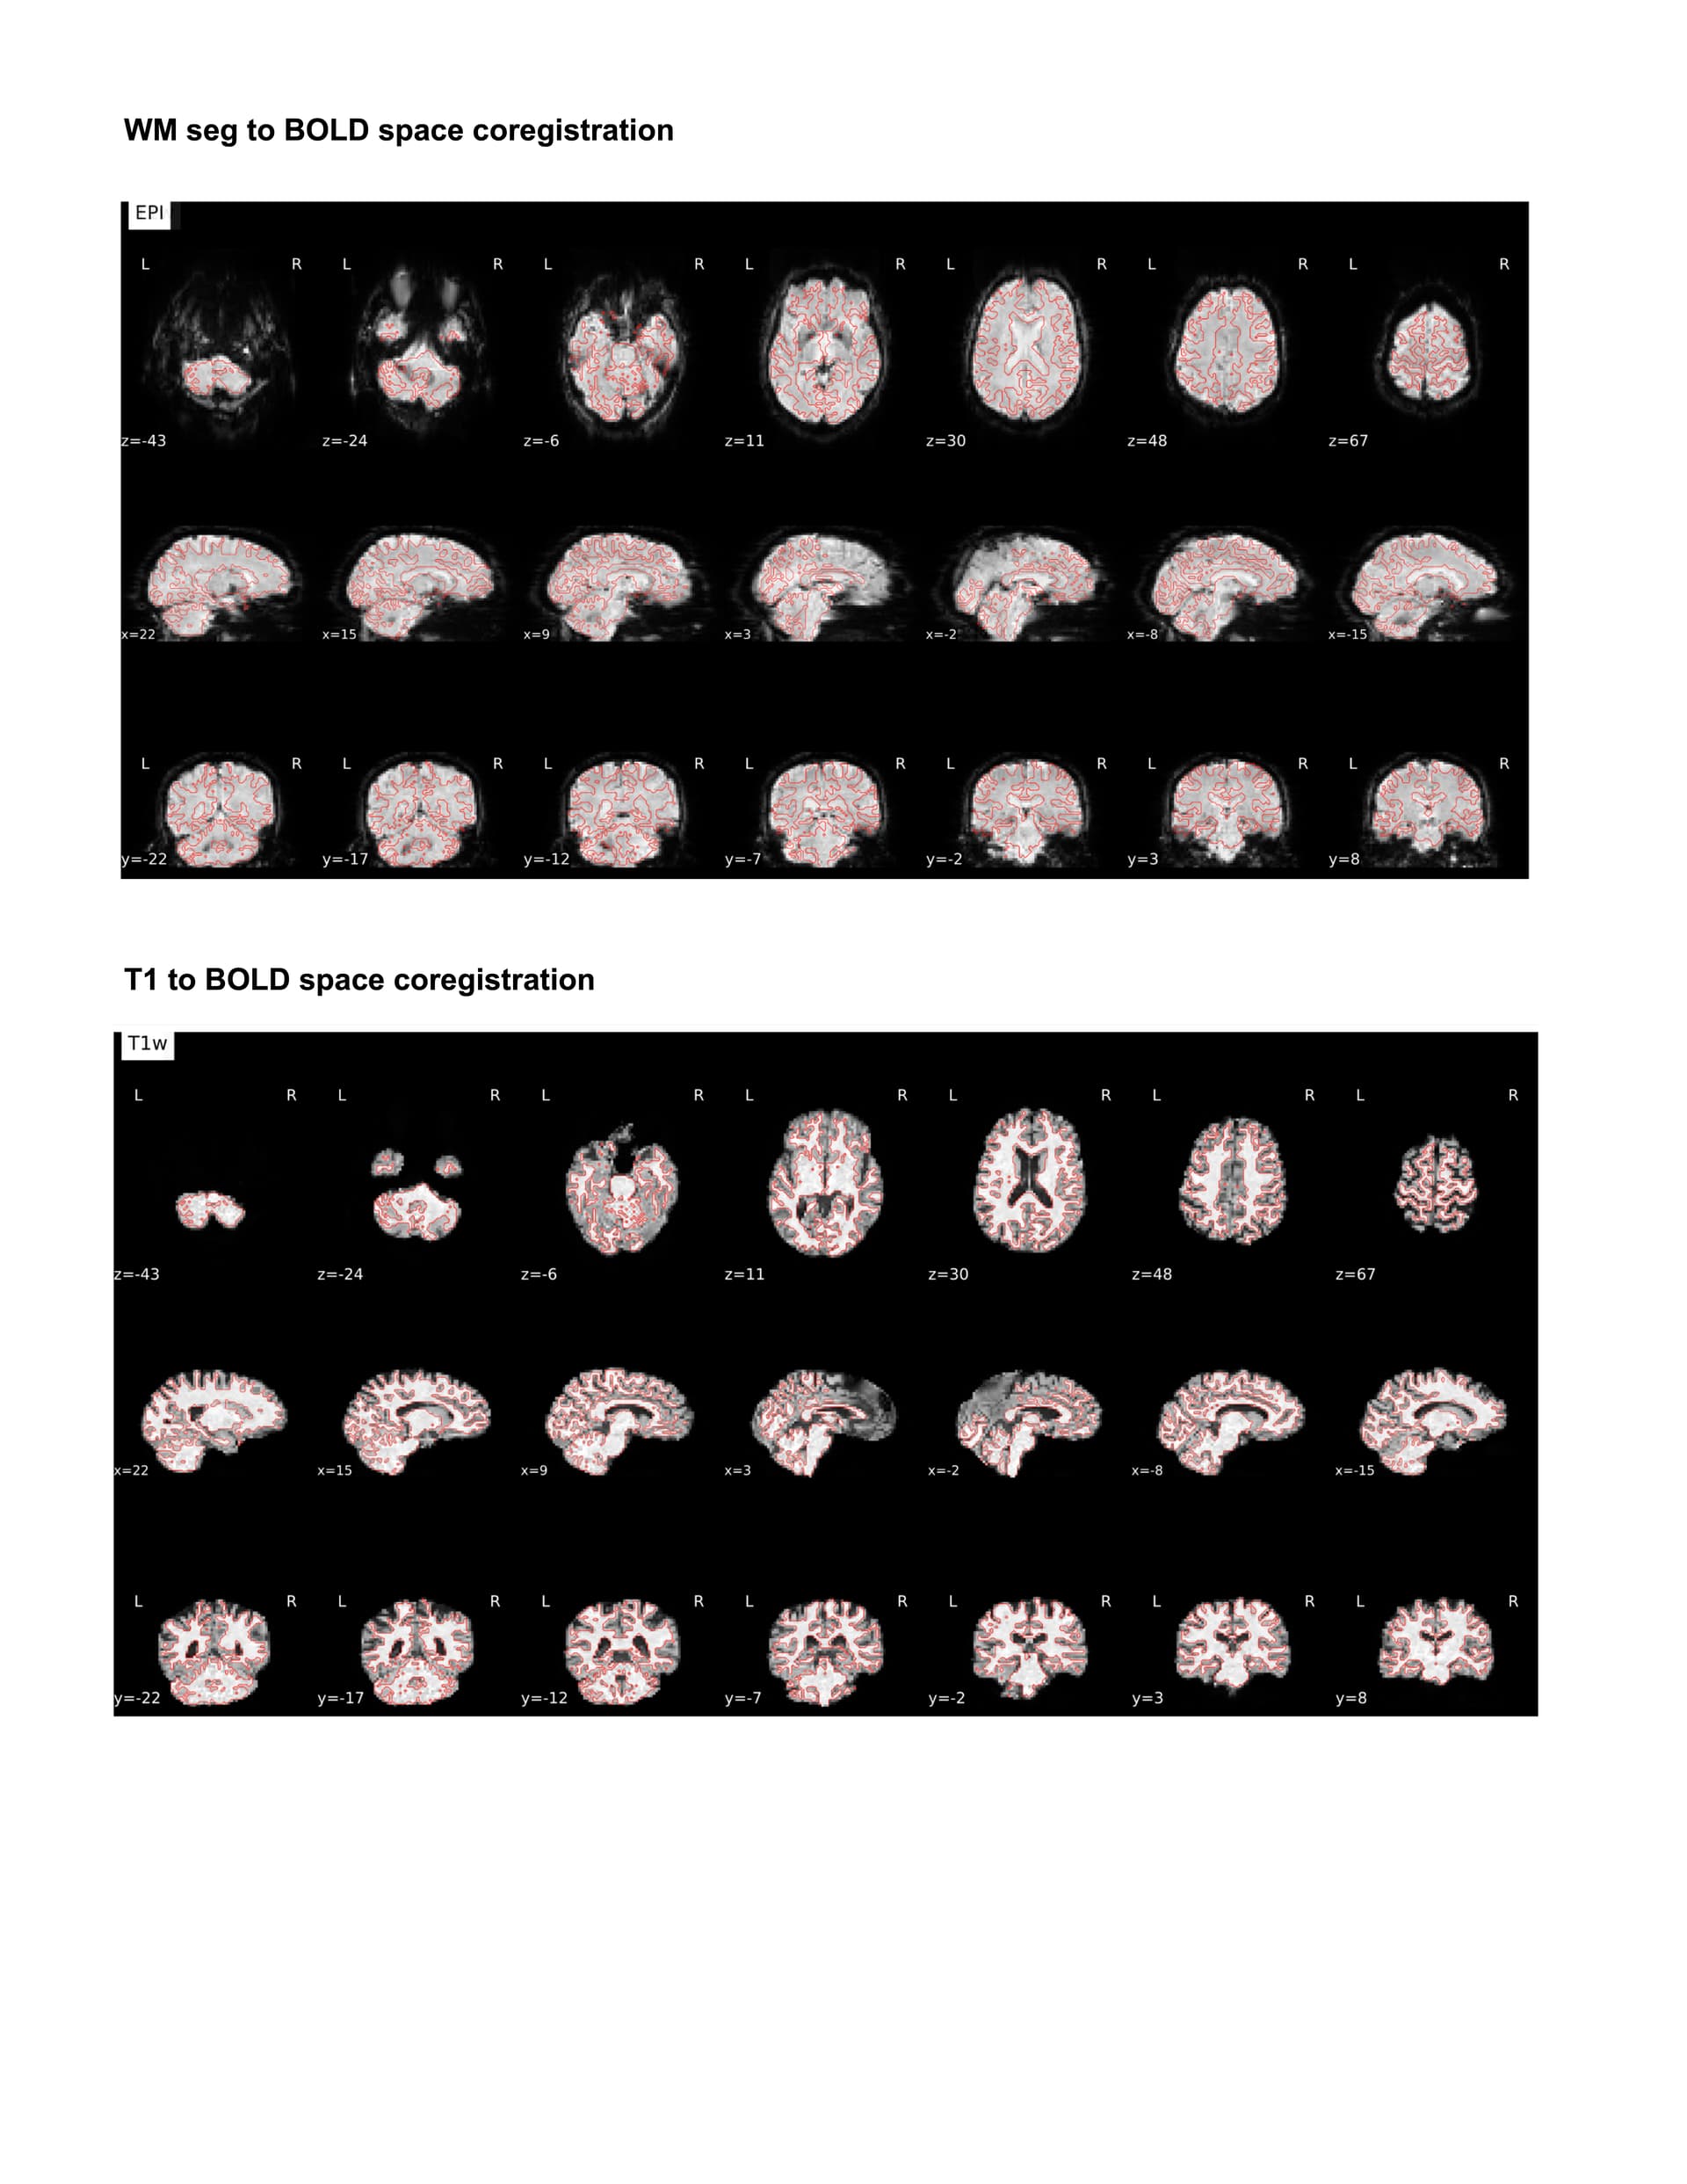

For my dataset I have found that ANTspyNET consistently produces a good/clean brain mask compared to fmriprep (antsBrainExtraction x Freesurfeer method). The default fmriprep method often outputs brain mask/segmentations that include the skull/non-brain tissues. As a result, I have been feeding my ANTspyNET mask as input via the --derivatives flag. While this works and the resulting outputs look good (see attached screenshots: decent tissue segmentations, good BOLD-T1 coreg etc), I noticed that the preprocessed anatomical T1 gets skull stripped in the process. Is this a sign of something going wrong under the hood?